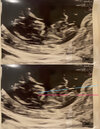

Melduje się po badaniu, ależ odetchnęłam!! Moje obie dwie myszki maja się bardzo dobrze, wiek ciąży zgodny z OM, dwa serduszka biją

dzieciaczki są najpewniej dwujajowe i na szczęście dwuowodniowe, nie widać jeszcze ilu kosmówkowe. Jak machały mi rączką to poszły łzy szczęścia

Wrzucę Wam zdjęcie usg jak będzie już grupa prywatna. Termin 31.12-3.01 ale ze względu na ciąże bliźniacza pewnie będzie CC odrobine wcześniej, także jestem grudniówką